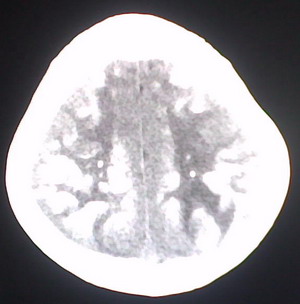

以下是引用jiajie在2009-2-3 20:02:00的发言:[br]脑室周围白质区可见大量斑片状钙化,部分融合成带状,双侧侧脑室及第三脑室扩大。[br]考虑弓形体原虫感染。(先天性宫内感染、torch综合症)

以下是引用lkc8963在2009-2-3 21:15:00的发言:[br]临床眼睑可见静脉扩张,ct双侧眼上静脉亦示扩张,颅内钙化以皮层\\软脑膜为主而不是位于白质和室管膜,再加上静脉窦异常,还是应该考虑静脉血管瘤病,可能为较复杂的血管畸形.

以下是引用卜一在2009-2-4 9:21:00的发言:[br]sturge-weber综合征:面部三叉神经分布区的毛细血管性或海绵状血管瘤以及同侧枕、顶或额叶软脑膜的血管瘤(以静脉性为主)。脑皮质,特别是第二三层,毛细血管可有增厚和钙化。局部发生层状坏死、神经细胞脱失、萎缩、胶质细胞增生及钙盐沉着。可根据面部典型分布的特征性皮痣作出诊断。头颅ct:发现面部血管瘤同侧的脑内病理钙化影,呈双层线条波浪形、脑回形或树枝形。本例支持:sturge-weber综合征![br]